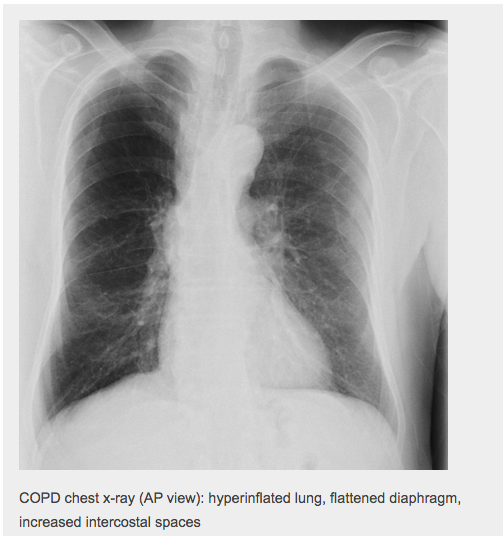

State some signs of hyperinflation on CXR